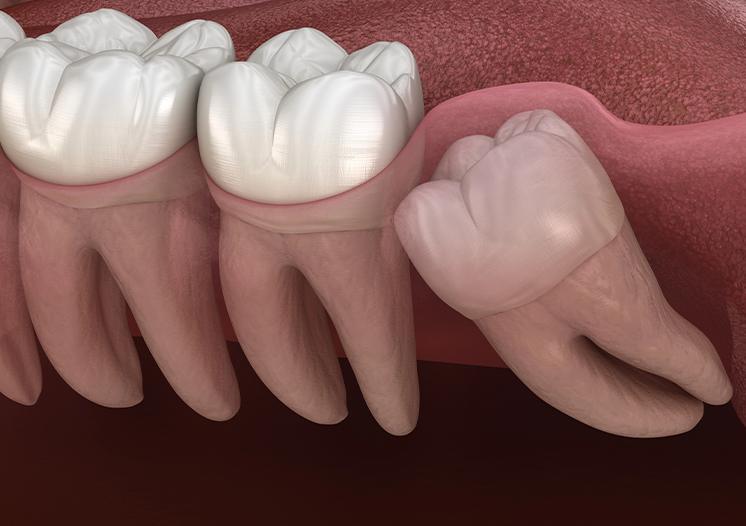

● Teeth growing at an angle and affecting nearby teeth

● Impacted teeth that remain under the gums or bone

Wisdom teeth removal can vary depending on how the teeth are positioned. Some teeth are easier to remove, while others may require a more involved approach. Our team will explain what applies to your situation so you know what to expect before your appointment.